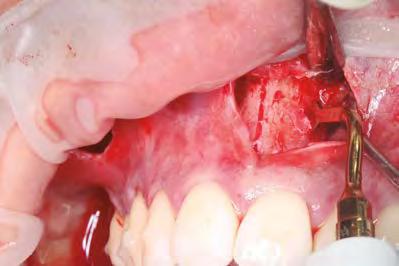

–Corticotomías y Ortodoncia. Ampliando límites del movimiento dental, por la Dra. Aranzazu Senosiain y cols. [50]